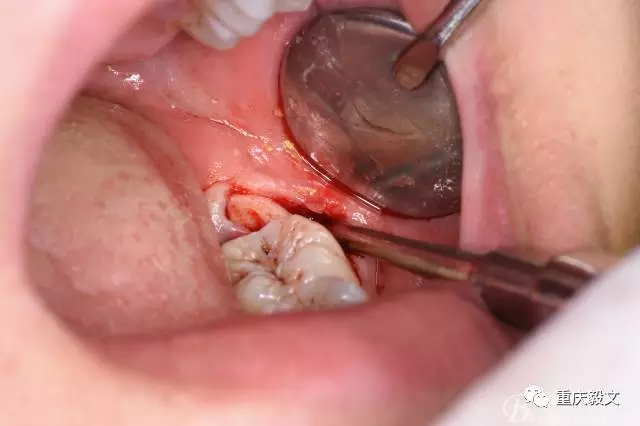

圖9.再把38牙冠近遠(yuǎn)中縱斷

圖10.用丁字挺取出牙冠舌側(cè)部分

圖11.取出的38舌側(cè)部分

圖12.接著取出38的頰側(cè)部分牙冠